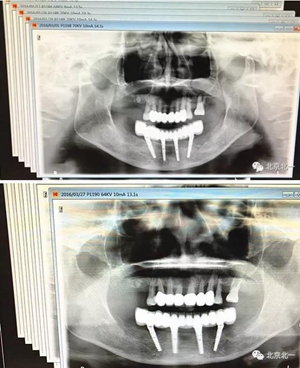

圖二十二:2015年到2016年復(fù)查時(shí)X片 ,有圖有真相

沒有假貨,貨真價(jià)實(shí),完成三年復(fù)查。

圖二十三:有圖有真相。

圖二十四:2017年11月復(fù)查時(shí)照片,植體很穩(wěn)定, 無骨吸收。